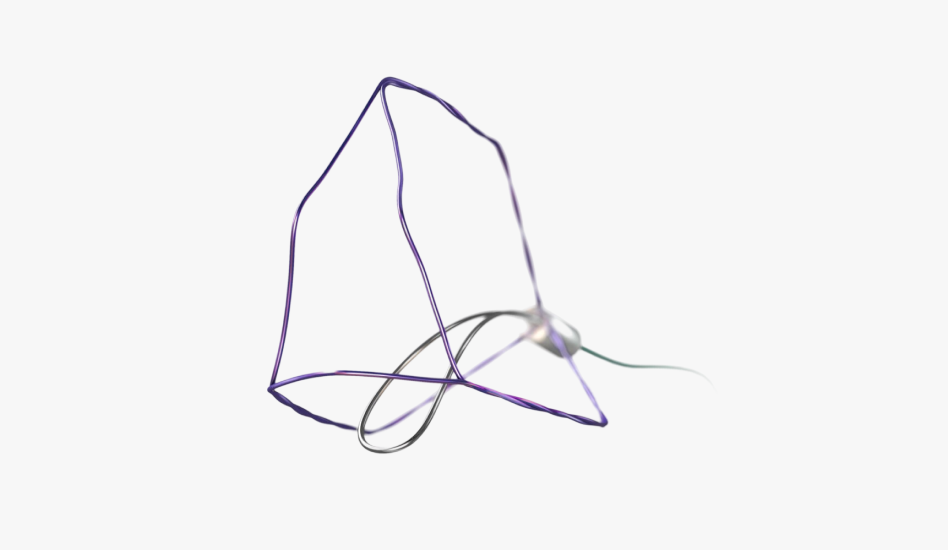

아이틴드 시스템 (전립선 스텐트)

아이틴드 시스템 (전립선 스텐트) -